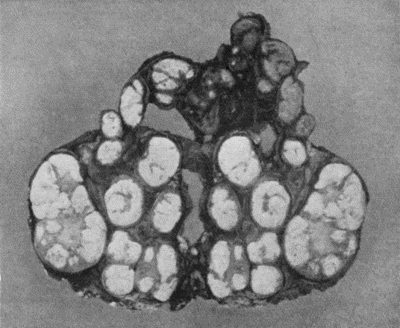

59.Dermoid Cyst of Ovary 213

60.Carpal Ganglion in a woman æt. 25 215